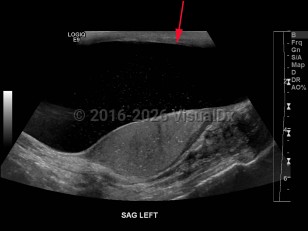

Imaging Studies image of Hydrocele of testis - imageId=8358988. Click to open in gallery.  caption: '<span>Grayscale ultrasound image of the scrotum demonstrates a large hydrocele with debris on the left.</span>'

Grayscale ultrasound image of the scrotum demonstrates a large hydrocele with debris on the left.